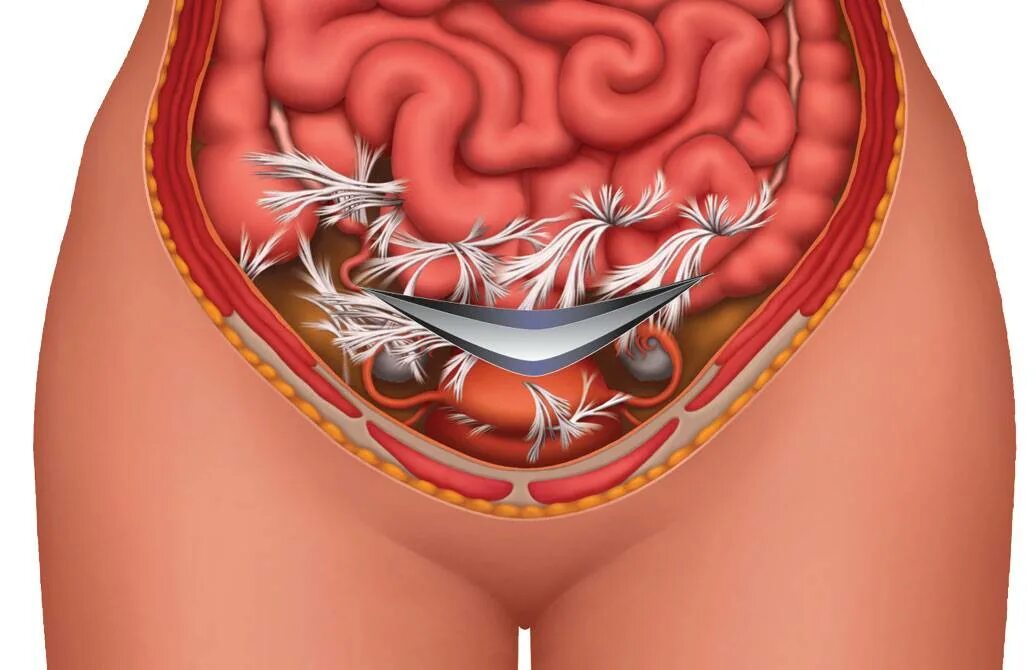

Рубец на матке мкб